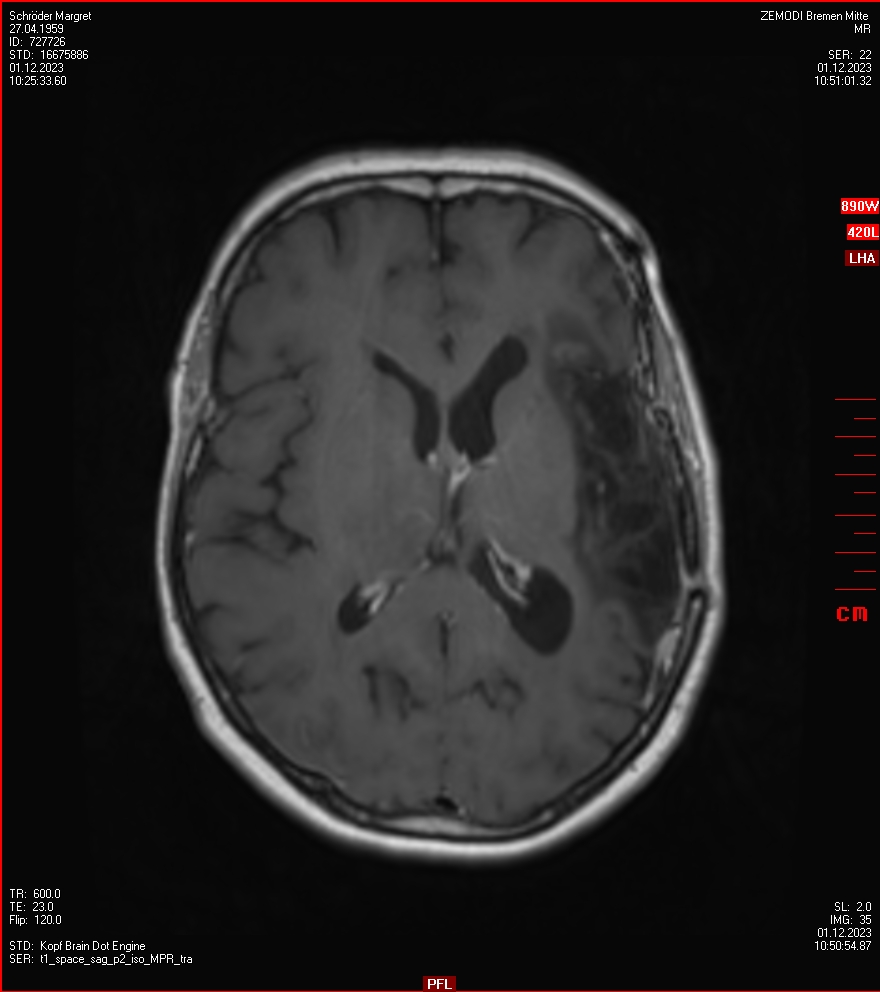

Zum Vergleich nun auch die Bilder vom 1.12.2023:

Ich denke, in den letzen 12 Monaten sind da ein paar Rezidive gewachsen,  vor 12 Monaten waren sie auch schon zu erkennen - vorher noch nicht. Nun hoffe ich auf den Rat des Spezialisten. Hoffendlich kann man etwas machen.